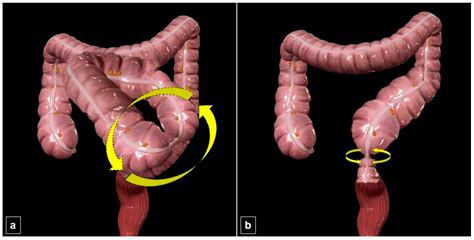

The Birdbeak Sign is a distinctive radiographic appearance seen on abdominal X-rays or CT scans. It is characterized by a tapered, beak-like appearance of the sigmoid colon, which indicates a twist or volvulus. This sign is crucial because it helps radiologists and gastroenterologists identify the presence of a sigmoid volvulus, which is a medical emergency requiring immediate intervention.

Management of Sigmoid Volvulus

Once a sigmoid volvulus is diagnosed, prompt management is essential to prevent complications such as ischemia and perforation. The management strategies include:

• Endoscopic Detorsion: This involves using the sigmoidoscope to untwist the colon. This procedure can be performed during the flexible sigmoidoscopy and is often the first-line treatment.

• Surgical Intervention: In cases where endoscopic detorsion is not successful or if there are signs of ischemia, surgical intervention may be necessary. This can involve a sigmoid colectomy, where the affected portion of the colon is removed.